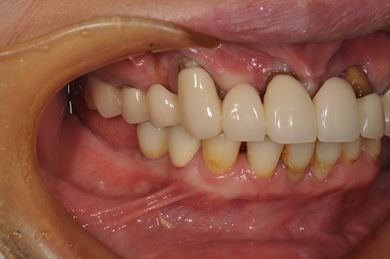

インプラントの症例写真 IMPLANT

インプラント治療+セラミック治療

| 主訴 | 上の奥歯がむし歯で治したい。下の歯が少ないので、インプラントか入れ歯、できれば併用で。 | ||||||||||||||||||||||||||||||||

| 治療方針 | インプラント治療にて、機能的・審美的回復を行う。 | ||||||||||||||||||||||||||||||||

| 治療内容 | インプラント3本、ハイブリッドセラミッククラウン5本 | ||||||||||||||||||||||||||||||||